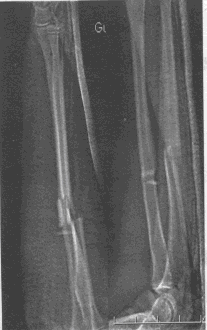

患儿男,9岁,摔伤致右前臂疼痛、肿胀、活动障碍3小时,查体:右前臂肿胀明显,局部压痛,可见瘀斑,可触及骨擦感。

第1题,共6个问题

(单选题)该患者X线片检查结果如下 :该部位骨折,最有可能合并()

第2题,共6个问题

(单选题)该患者应该首先接受的检查是()

第3题,共6个问题

(单选题)该患者应该首先考虑的诊断是()

第4题,共6个问题

(单选题)该患者最可能出现的远期并发症是()

第5题,共6个问题

(单选题)该患者的首选的治疗方案是()

第6题,共6个问题

(单选题)随访2个月,肘关节屈伸活动度30~110度,则应()